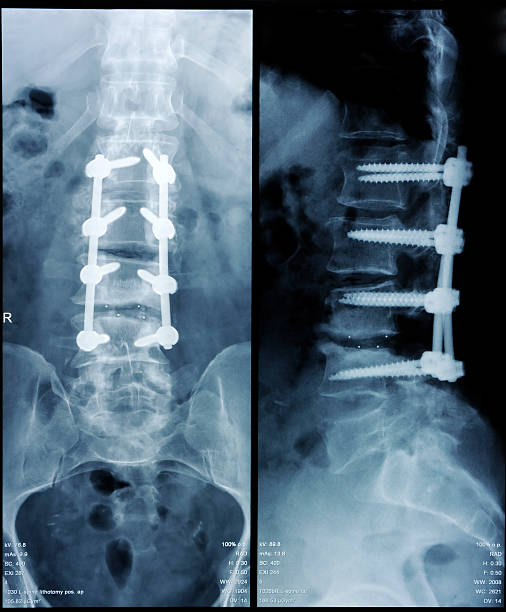

척추 안정화 수술

척추 안정화 수술은 척추의 안정성을 높이기 위해 나사나 철사 등의 재료를 사용하여 수행되는 수술입니다. 우리 몸의 기둥과 같은 역할을 하는 척추는 일상생활에서 많은 무게와 압력을 버티며 지지해야 합니다. 하지만 일부 환자들은 척추에 문제가 발생하여 이상적인 정렬과 안정성을 유지하기 어려워 통증과 불편을 겪습니다. 이런 상황에서 척추 안정화 수술은 해결책이 될 수 있습니다.

척추 안정화 수술은 크게 두 가지 방법으로 시행됩니다. 첫 번째 방법은 나사를 사용하여 척추를 안정화하는 것으로, 피부 절개를 통해 척추의 이상 부위에 나사를 박아서 척추를 고정시킵니다. 두 번째 방법은 철사를 사용하여 척추를 연결하는 것으로, 나사와 함께 사용되기도 합니다. 척추 안정화 수술은 척추의 이동성을 제한하여 통증을 줄이고 척추를 더 안정적으로 만듭니다.